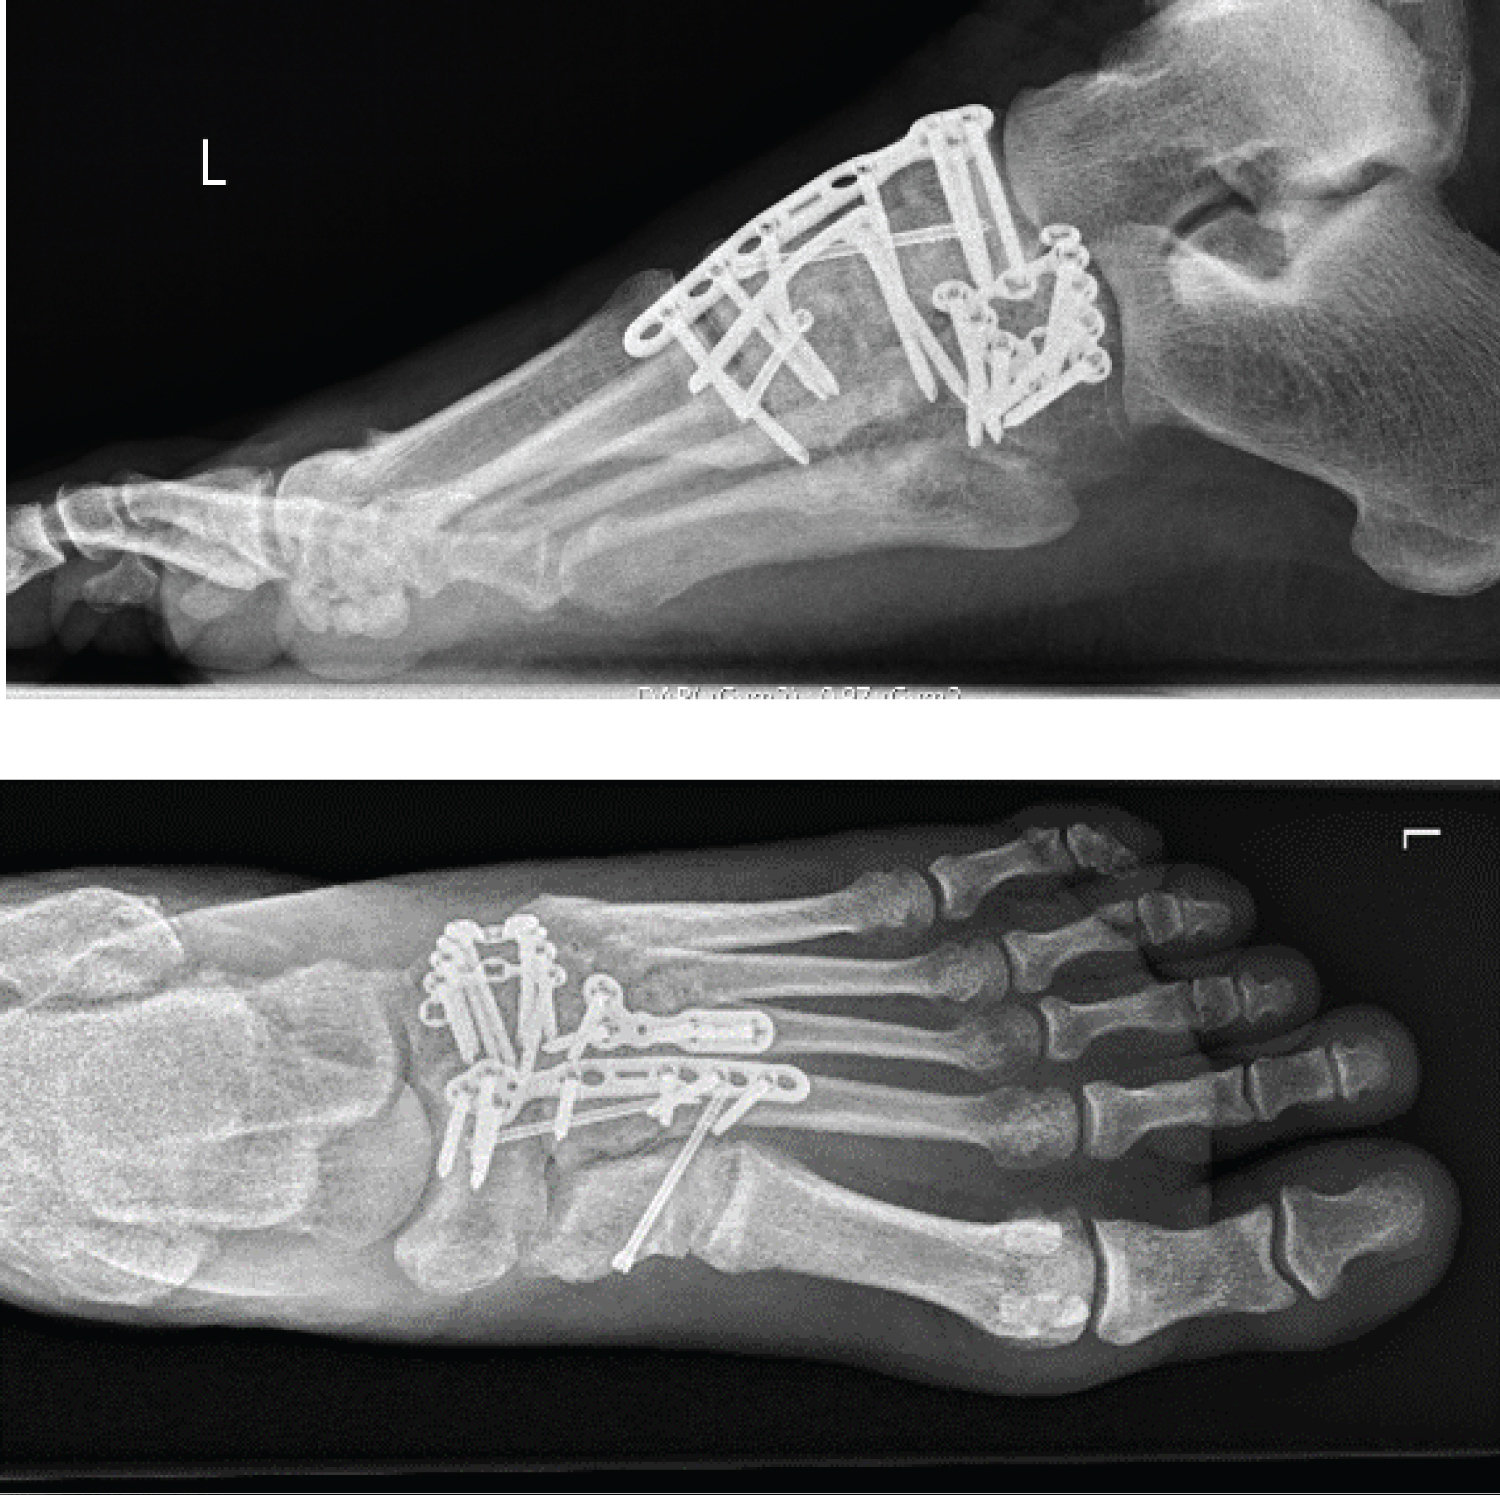

The open reduction and internal fixation of the cuboid bone was done via a second approach. After anatomical reduction of the comminuted fracture of the cuboid bone with fragments going into the fourth and fifth tarsometatarsal articular surfaces, the fracture was fixed with a slightly pre-bent locking cuboid plate (Figure 3).

Figure 3: Post-operative X-rays ap/lat. View Figure 3